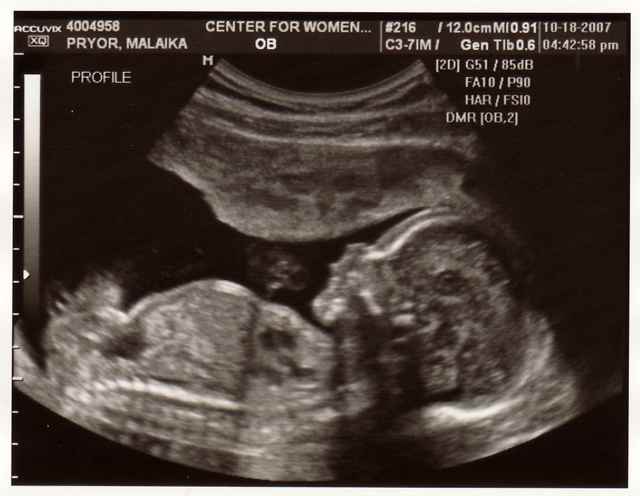

5 неделя. Побежала на УЗИ, так не терпится узнать, что там. Результат УЗИ – плод 1, 5 недель беременности, похож на маленькую фасолинку. Фуууух, один! Я боялась, что будет двойня, как у мамы.

12 неделя. Неужели мальчик? Узист сказала: похож на мальчика. Звучит, как приговор. Но так как мы хотим барышню, решили не верить и никому не говорить. Ждем 20-й недели, тогда уж точно станет ясно, кто у меня внутри. Но если пацан, то мне еще нравятся имена Георгий и Герман. И Алексей, Лешка. Но Лешек у нас в семье и так навалом.

![]() |

Осень нынче просто чудо! Доктор прогнозирует кузнечика в 3700 гр. и 53-54 см. в 27 недель и 3 дня – 1150 гр., стопа 6 см, личико опять не показал. Прочитала Маркеса и Гальего. Осень же. Осенью всегда читаю Маркеса, он лечебный.

32 неделя. Плохо сплю. Кузнечик 1820 гр. и уже с прической! Прямо видно на УЗИ, что волосы на голове у человека. Вот это чудо! Уверена, что у меня внутри лохматый черныш, похожий на мужа. В больнице жутко, ночью некоторых увозят на каталках рожать, топают над головой, все беременные какие-то сонные.